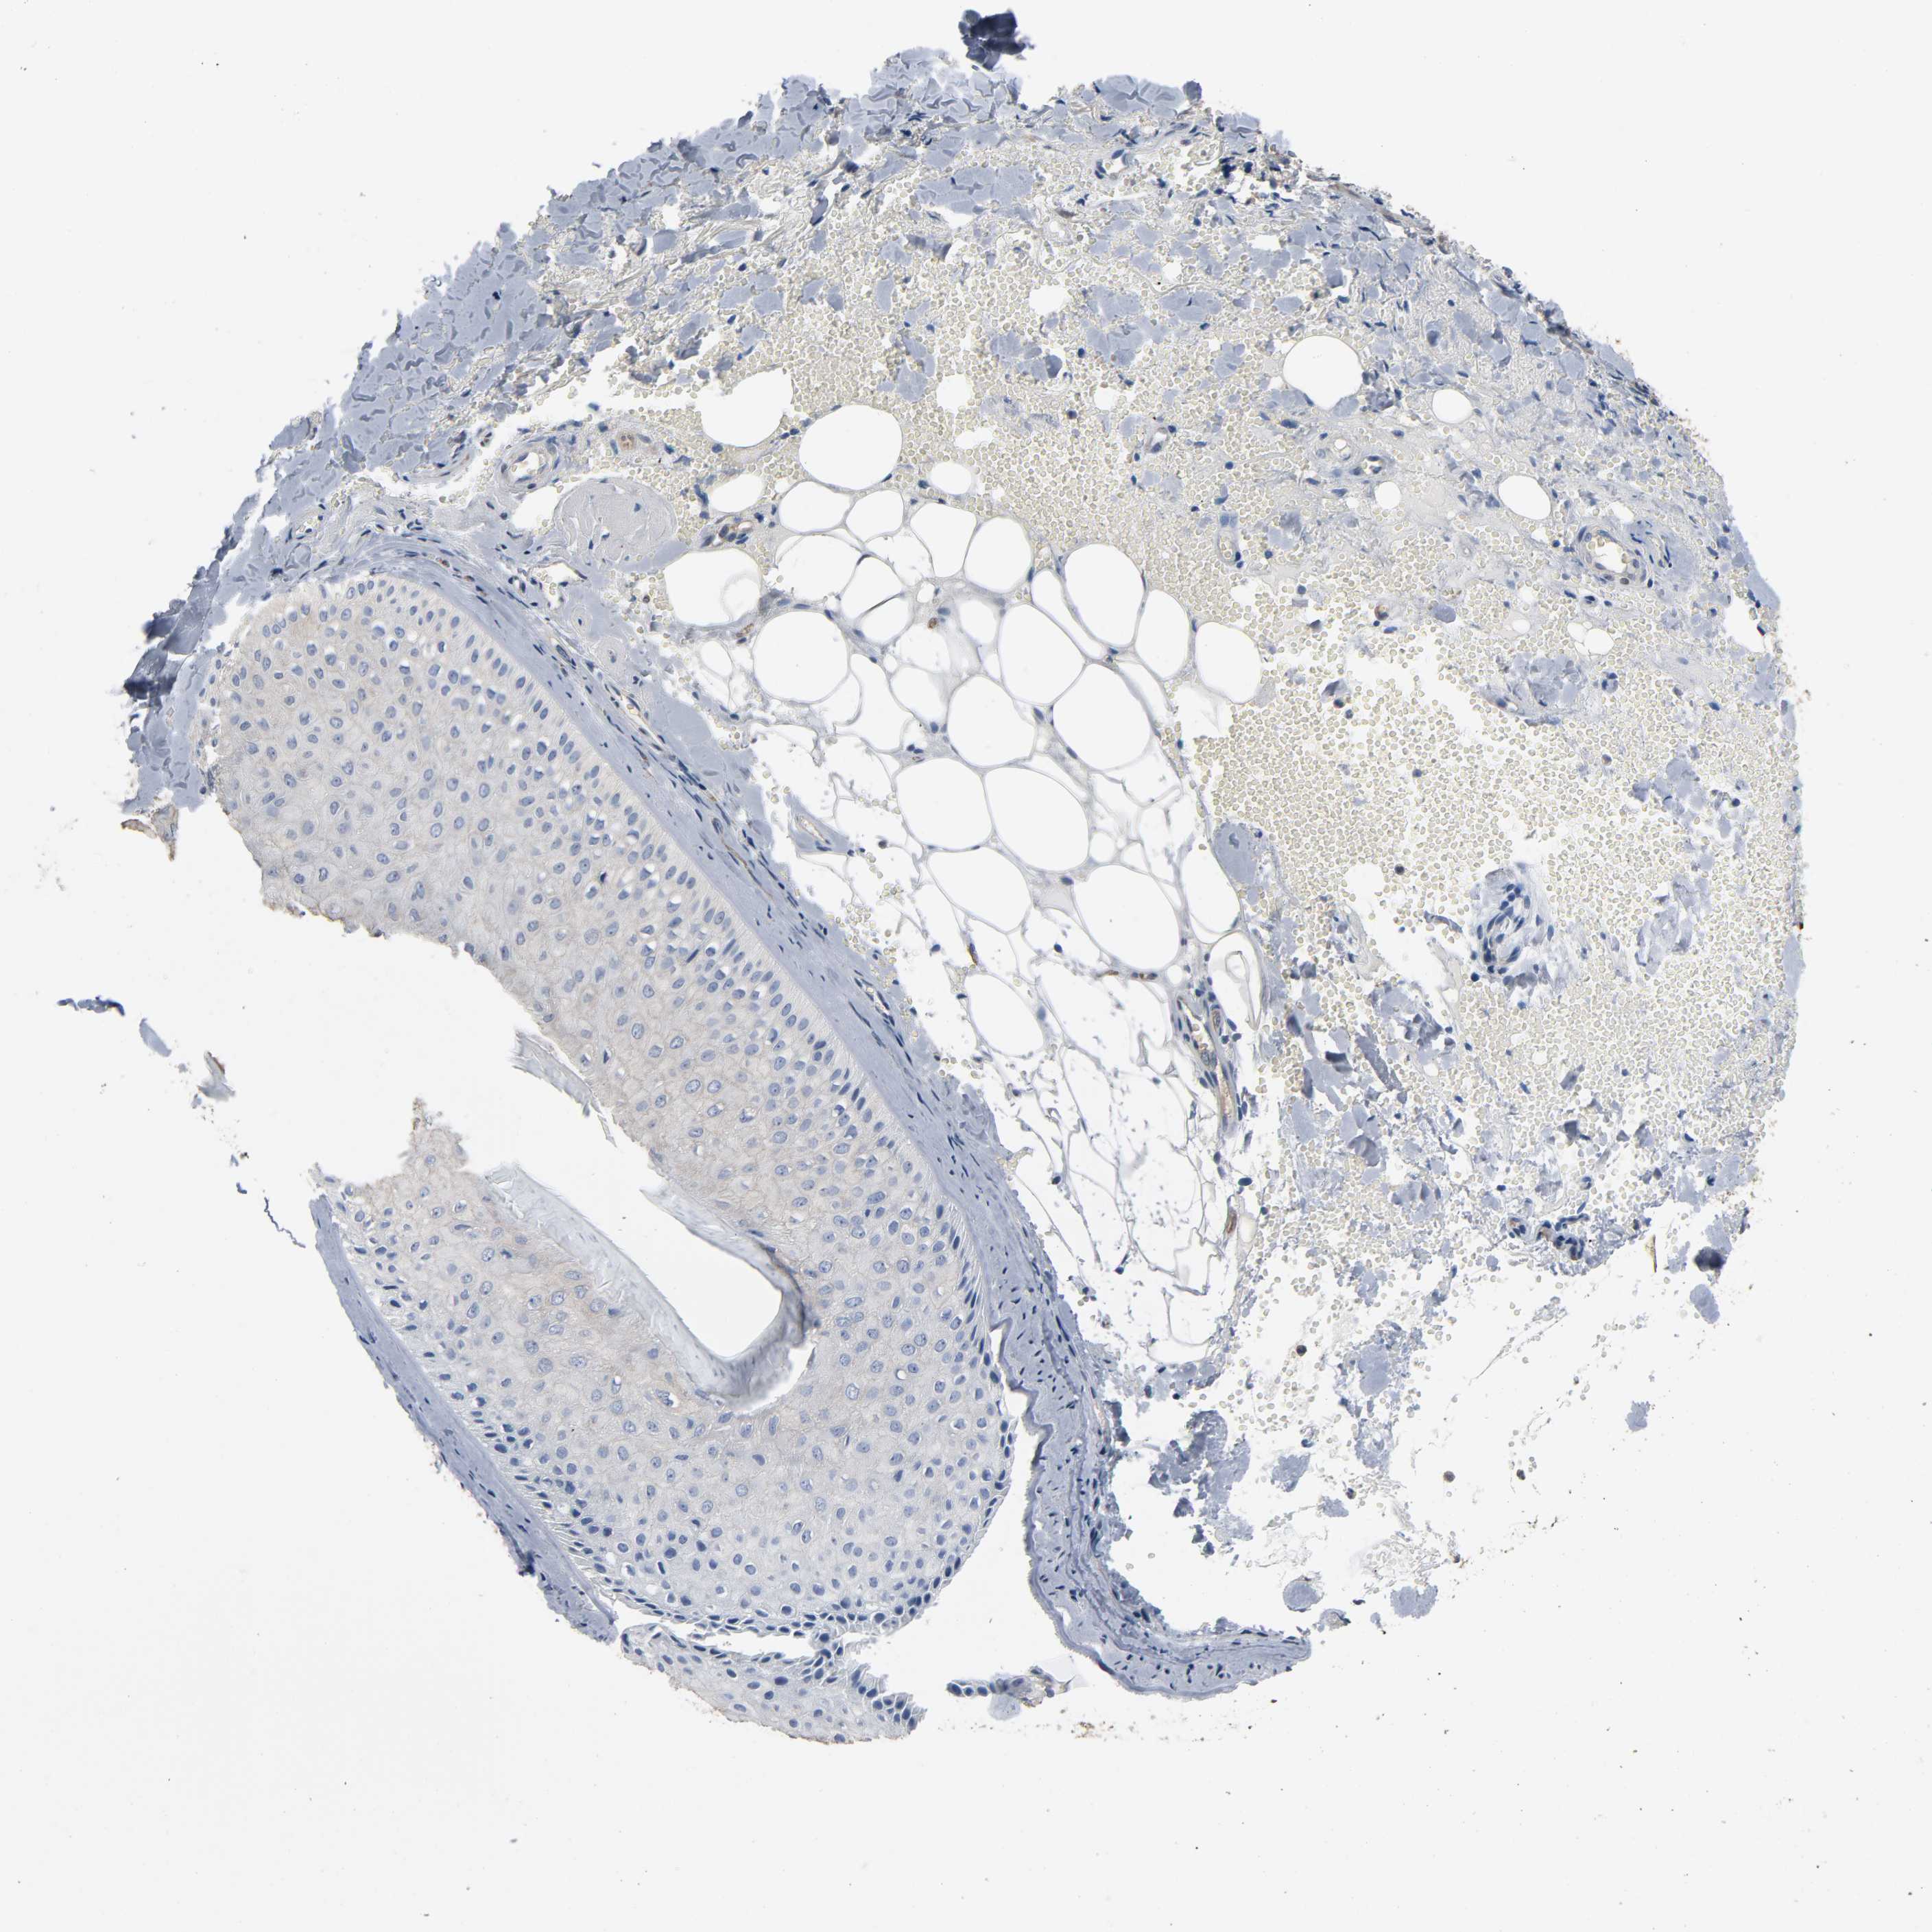

Basal cell and squamous cell cancer

SKIN CANCER - Protein expressioni

A mouse-over function shows sample information and annotation data. Click on an image to view it in a full screen mode. Samples can be filtered based on level of antibody staining by selecting one or several of the following categories: high, medium, low and not detected. The assay and annotation is described here.

Antibody stainingi

Antibody staining in the annotated cell types in the current human tissue is reported as not detected, low, medium, or high, based on conventional immunohistochemistry profiling in selected tissues. This score is based on the combination of the staining intensity and fraction of stained cells.

Each image is clickable and will lead to virtual microscopy that enables deeper exploration of all samples and also displays staining intensity scores, fraction scores and subcellular localization as well as patient and tissue information for each sample.

Antibody HPA001923

Antibody HPA003908

Staining

High

Medium

Low

Not detected

Intensity

Strong

Moderate

Weak

Negative

Quantity

>75%

75%-25%

<25%

None

Location

Nuclear

Cytoplasmic/membranous

Cytoplasmic/membranous,nuclear

Squamous cell carcinoma, NOS

Basal cell carcinoma